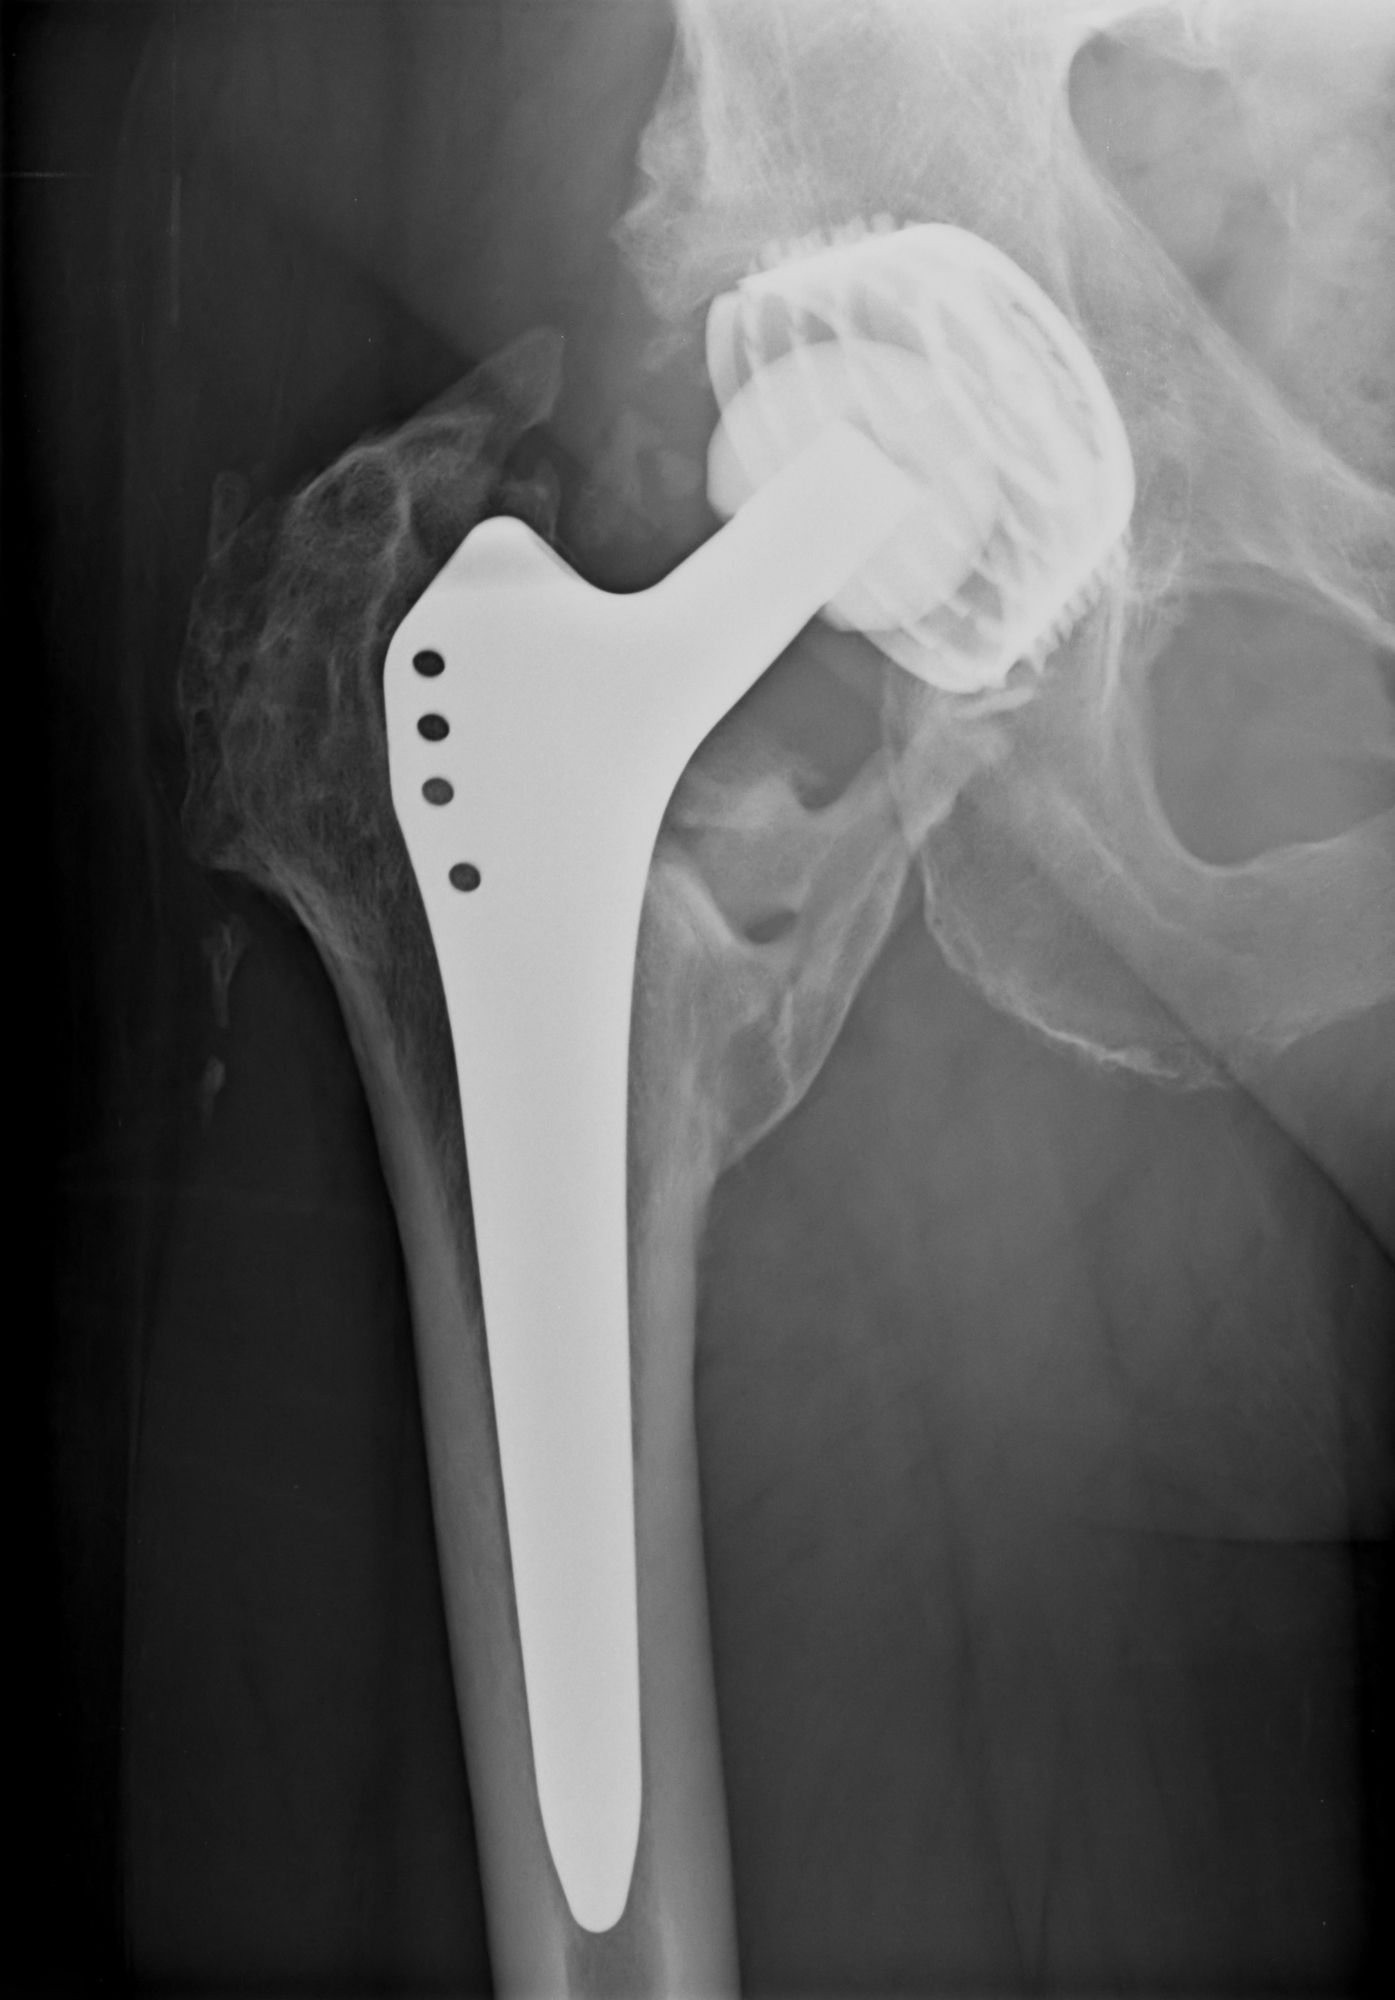

Ceramic Hip Replacements in West Sussex Mr Nirav Shah Hip Replacement Recall Metal Toxicity A painful mom hip arthroplasty has various intrinsic and extrinsic causes (table 1). In mom hip implants, the. Metal‐on‐metal (mom) hip resurfacing has recently been a popular prosthesis choice for the treatment of symptomatic. Cobalt was widely used for hip and knee joint replacements until cases of heavy metal poisoning appeared. Hundreds of thousands of patients around the world may. Hip Replacement Recall Metal Toxicity.

Fracture After Total Hip Replacement OrthoInfo AAOS Hip Replacement Recall Metal Toxicity A painful mom hip arthroplasty has various intrinsic and extrinsic causes (table 1). Hundreds of thousands of patients around the world may have been exposed to toxic substances after being implanted with poorly regulated and potentially dangerous hip. As in all painful tha,5 a thorough clinical history, a. Metal‐on‐metal (mom) hip resurfacing has recently been a popular prosthesis choice for. Hip Replacement Recall Metal Toxicity.

Fracture After Total Hip Replacement OrthoInfo AAOS Hip Replacement Recall Metal Toxicity A painful mom hip arthroplasty has various intrinsic and extrinsic causes (table 1). Hundreds of thousands of patients around the world may have been exposed to toxic substances after being implanted with poorly regulated and potentially dangerous hip. As in all painful tha,5 a thorough clinical history, a. In mom hip implants, the. Metal‐on‐metal (mom) hip resurfacing has recently been. Hip Replacement Recall Metal Toxicity.